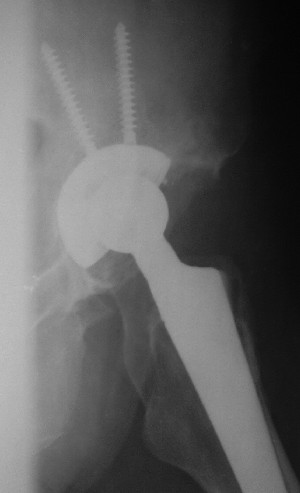

После протезирования боковой 5/04/04

Больной 18 мая 2003 года в автоаварии получил перелом левой вертлужной впадины, вывих бедра. Госпитализирован в один из стационаров области.Вывих вправлен. В последствии бедро вывихивалось еще дважды. На консультацию был представлен снимок от 19.05.03г., больной переведен к нам 3.06.03г. Снимок при поступлении - перелом впадины, задне-верхний вывих бедра. 05.06.2003 г. выполнено открытое вправление вывиха левого бедра и остеосинтез стенки вертлужной впадины двумя винтами. Послеоперационный период без осложнений. Объем движений в левом тазобедренном суставе восстановился полностью. Выписан на амбулаторное лечение в удовлетворительном состоянии с рекомендациями 3 месяца ходить на костылях без нагрузки на оперированную конечность. На контрольных рентгенограммах левого тазобедренного сустава 13.10.2003 г. - признаки консолидации перелома; плотность, форма головки и состояние суставных поверхностей удовлетворительные. Разрешена дозированная осевая нагрузка, на конечность с использованием дополнительной опоры. 19.12.2003 г. больной обратился с жалобами на боли в левом тазобедренном суставе. На рентгенограммах левого тазобедренного сустава 19.12.2003 г., 20.02.04г. - асептичекий некроз головки бедра. 5.04.04г. - эндопротез. Сейчас ходит без трости, не хромает. Особенность эндопротезирования - при удалении винтов прослежена линия перелома заднего края впадины и предложено установить чашку несколько меньшего диаметра, чтобы она была покрыта несломанной частью.